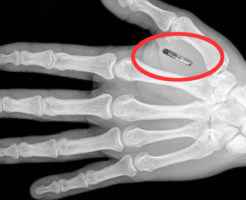

便利だけど危険?日本で体内「ICチップ」普及の議論(海外の反応)海外の反応 センサーにかざすだけで解錠や電子承認ができる極小のICチップを手など体内に埋め込む人が国内に出始めた。利用者は30人以上に上るとされ「人間と機械の融合」に向けた第一歩の技術と歓迎するが、日本では医師以外が他人へ埋め込むと […] 続きを読む